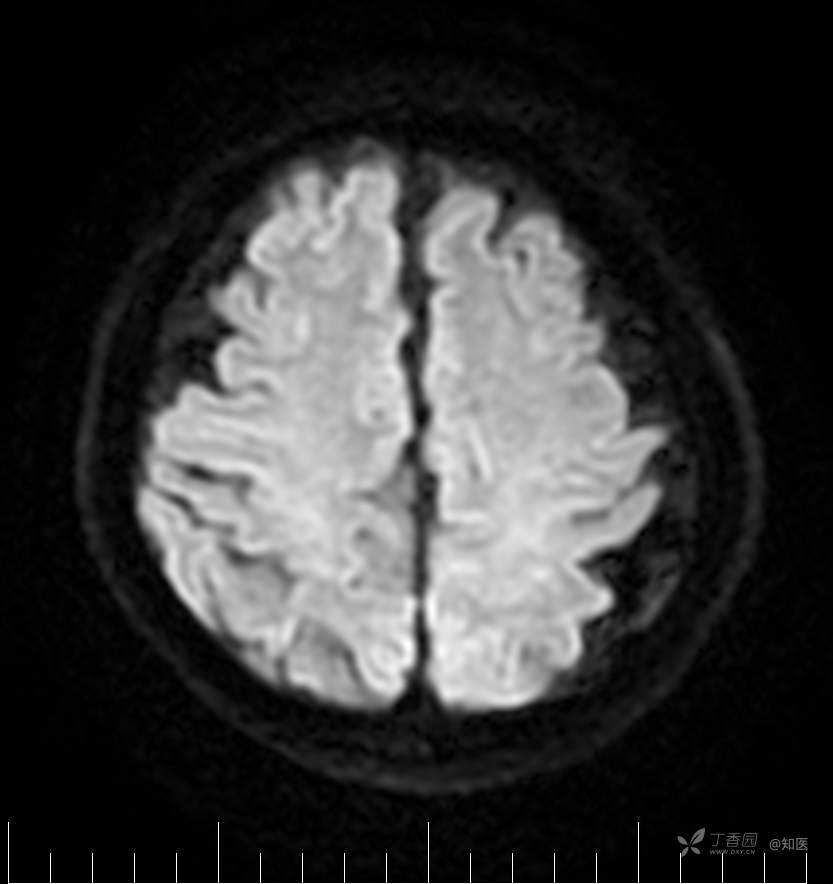

2021-6-15 DWI

2021-06-16日晨查房,患者自觉入院治疗后肢体无力症状较前稍改善,仍有活动后气短,余未诉特殊不适。ALSFRS-R评分:44分(单项均大于等于2分)。血压:123/63mmHg。神经系统查体:GCS 15分,右利手,查体合作,问答切题,粗测智能基本正常。额纹对称,双眼闭目紧,双侧瞳孔等大等圆,直径约3.0mm,对光反射灵敏,眼球运动自如,无眼震,双侧鼻唇沟对称等深,口角无歪斜。悬雍垂居中,双侧软腭抬举良好,咽反射灵敏、转颈、耸肩均一致有力。颈屈肌、颈伸肌力量5级。伸舌居中,无舌肌纤颤及萎缩。双侧岗上肌、岗下肌可见萎缩;双侧三角肌可见偶发肉跳、肌力5级,左侧肱二头肌肌力4+级、右侧4-级,双侧肱三头肌肌力4+级;双手握力可,双手大小鱼际肌及第一骨间肌可见萎缩,左侧明显,左侧手腕背伸力量4级、右侧4+级,双侧拇短展肌肌力4-级,双侧示指伸肌肌力3级,左侧指总伸肌肌力4级、右侧4-级,双侧小指展肌肌力4-级。双上肢肌张力对称减低。左侧肱二头肌反射迟钝、右侧未引出,双侧桡骨膜反射及肱三头肌反射未引出。左侧胸大肌反射阳性、右侧未引出,双侧Rossolimo征阳性、Hoffmann征阴性,下颌反射阴性。腹壁反射未引出。双下肢可见肌肉萎缩,以左侧明显;左侧髂腰肌肌力4级、右侧4-级,双侧股四头肌肌力5级,双足背伸力量3级,左足跖屈力量4级、右足4+级。双下肢肌张力对称基本正常。双侧膝腱反射、跟腱反射迟钝,双侧跖反射消失,双侧巴氏征未引出。右侧大腿外侧肌肉活检瘢痕周围浅感觉缺失,余肢体及躯干深浅感觉正常,共济运动对称正常。颈软,无抵抗,双侧布氏征及克氏征均阴性。辅助检查:微量元素(钙、镁、铁、铜、锌),微量元素测定(铅,镉)[复][2021-6-16 16:11:07]:钙1.19mmol/l;铁9.00mmol/L。急诊电解质七项[复][2021-6-16 10:41:41]:钾3.55mmol/L。血细胞分析+五分类[2021-6-16 9:57:17]:淋巴细胞百分比19.5%。[头颅,扩散成像(DWI)][头颅,磁敏感成像(SWI)][头颅,水抑制成像(FLAIR)][2021-6-16 18:10:50]:1.多发腔梗,脑白质脱髓鞘,脑萎缩。2.DWI:脑实质内未见明显高信号。3.磁敏感成像脑实质内未见明显异常信号灶。MMSE:26分(高中文化水平)。MoCA:23分。ADL评分:14分。ECAS评分:96分(ALS特异67分、ALS非特异29分)。肌电图:提示颈髓、腰髓、胸髓和延髓支配肌肉可见活动期神经源性损害,颈髓和腰髓支配肌肉同时可见慢性期神经源性损害;提示脊髓前角细胞损害可能,请结合临床。心电图大致正常。外送基因检查:TBK1基因杂合子,提示额颞叶痴呆和(或)肌萎缩性侧索硬化症4型。二线主治医师查看患者后示:1.患者基因检查结果显示TBK1基因杂合子,提示额颞叶痴呆和(或)肌萎缩侧索硬化症4型,结合外院影像学检查可见额颞叶萎缩明显,来院后复查头颅FLAIR+DWI+SWI亦提示脑萎缩,量表评估提示认知功能稍减退,ECAS评分基本正常。综上,修正诊断:肌萎缩侧索硬化症(ALS) 额颞叶变性 低钾血症 高血压2级(高危) 多发腔隙性脑梗死。因TBK1基因引起的额颞叶痴呆和(或)肌萎缩侧索硬化症为常染色体显性遗传,患者父亲已逝,母亲健在,诉无明显认知功能障碍或肌肉萎缩等表现,建议患者母亲抽血送检,进一步明确致病基因来源,必要时患者子女也可行基因检查进一步明确。2.患者目前诊断基本明确,根据文献报道,合并FTD的ALS患者整体生存周期较短(约19个月),目前患者发病已1年余,应充分与患者家属沟通病情,告知疾病预后及生存周期情况,同时建议开始口服利鲁唑片,延缓疾病进展。余治疗方案暂不予调整。密观病情变化,遵嘱执行。

2021-06-18出院总结: 卫某某,男,60岁,以“四肢僵硬1年,加重伴无力半年”之主诉入院。查体:生命体征平稳,心肺腹查体无明显异常。神经系统查体:GCS 15分,右利手,查体合作,问答切题,粗测智能基本正常。额纹对称,双眼闭目紧,双侧瞳孔等大等圆,直径约3.0mm,对光反射灵敏,眼球运动自如,无眼震,双侧鼻唇沟对称等深,口角无歪斜。悬雍垂居中,双侧软腭抬举良好,咽反射灵敏、转颈、耸肩均一致有力。颈屈肌、颈伸肌力量5级。伸舌居中,无舌肌纤颤及萎缩。左侧肱二头肌肌力4+级、右侧肱二头肌及双侧三角肌肱三头肌肌力5级;左手大小鱼际肌可见萎缩,左手握2指松、右手握力可,左手拇短展肌、示指伸肌、指总伸肌及抬腕力量3级,右手拇短展肌、示指伸肌、指总伸肌及抬腕力量4-级。双上肢肱二头肌反射、肱三头肌反射、桡骨膜反射均对称减低;双侧Hoffmann征、Rossolimo征、胸大肌反射及掌颏反射阴性,下颌反射阴性。双侧上、中、下腹壁反射可引出。左侧髂腰肌肌力4-级、右侧髂腰肌肌力4级,双侧股四头肌肌力5-级;右足背伸力量3级、左足背伸力量2级,双足跖屈力量5级。双下肢膝腱反射、跟腱反射对称减低;双侧膝阵挛、踝阵挛未引出。双侧巴氏征、Chaddock征均未引出。右侧大腿外侧肌肉活检处周围浅感觉减退,余四肢及躯干部深浅感觉正常,共济运动对称正常。颈软,无抵抗,双侧布氏征及克氏征均阴性。辅助检查:肌电图(2021-05-08,某军医大学附属医院):神经源性损害(颈段、腰骶段受累,胸段可疑;重复神经电刺激(低频、高频)可见左腋神经递减现象。 肌肉活检(2021-05-18,某军医大学附属医院):(右股四头肌)考虑神经源性损害,建议结合临床除外运动神经元病等。入院诊断:1.肢体无力:肌萎缩侧索硬化症(ALS);2.高血压1级(中危)。入院后查血清蛋白电泳:α2-球蛋白6.50%。凝血六项:血浆凝血酶原时间比值0.93;凝血酶原国际标准化比值0.93。贫血因子三项:维生素B12>1476.00pmol/L。平诊肝功十三项+平诊心肌酶谱五项+血同型半胱氨酸测定+平诊血脂八项+平诊肾功七项+平诊电解质八项:尿素3.05mmol/L;肌酐49umol/L;钾3.15mmol/L;高密度脂蛋白0.99mmol/L;载脂蛋白A1.131g/L;脂蛋白(a)333mg/L;肌酸激酶420U/L;总胆红素22.1umol/L;直接胆红素5.4umol/L。微量元素(钙、镁、铁、铜、锌),微量元素测定(铅,镉):钙1.19mmol/l;铁9.00mmol/L。急诊电解质七项:钾3.55mmol/L。血细胞分析+五分类:淋巴细胞百分比19.5%。[头颅,扩散成像(DWI)][头颅,磁敏感成像(SWI)][头颅,水抑制成像(FLAIR)]:1.多发腔梗,脑白质脱髓鞘,脑萎缩。2.DWI:脑实质内未见明显高信号。3.磁敏感成像脑实质内未见明显异常信号灶。MMSE:26分(高中文化水平)。MoCA:23分。ADL评分:14分。肌电图:提示颈髓、腰髓、胸髓和延髓支配肌肉可见活动期神经源性损害,颈髓和腰髓支配肌肉同时可见慢性期神经源性损害;提示脊髓前角细胞损害可能。血尿粪常规、免疫八项、风湿三项、血沉、传染指标、血同型半胱氨酸、糖化血红蛋白等未见明显异常。心电图、肺通气功能大致正常。住院期间给予营养神经、清除氧自由基等对症支持治疗。现患者诊断基本明确,生命体征平稳,一般情况良好,可予今日出院。出院诊断:1.肌萎缩侧索硬化症(ALS);2.额颞叶变性;3.低钾血症;4.高血压2级(高危);5.多发腔隙性脑梗死。出院医嘱:1.注意休息,加强营养,低盐、高蛋白高纤维素饮食,注意休息,适当锻炼,避免剧烈运动及重体力劳动。2.出院继续口服药物:甲钴胺 500ug/次,3次/日;辅酶Q10 10mg/次,3次/日;维生素E 100mg/次,2次/日;美金刚 10mg/次,1次/日;利鲁唑片,50mg/次,2次/日,与餐间隔1.5-2小时。3.出院继续用依达拉奉(必存)60mg+0.9%氯化钠 200ml,静滴,1次/日(首疗程14天,后每疗程10天,间隔20天,共使用6个疗程)。4.1月后门诊复查血常规、肝肾功能、电解质功能;3月后我科门诊再次复诊。5.不适随诊。